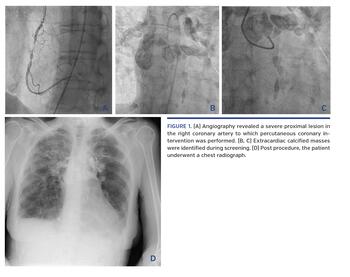

Angiography revealed a severe proximal lesion in the right coronary artery to which percutaneous coronary intervention was performed (Figure 1A). The patient experienced intermittent complete heart block during the procedure; she remained hemodynamically stable and pacing was not required. Extracardiac calcified masses were identified during screening (Figures 1B and 1C; Video 1).

Post procedure, the patient underwent a chest radiograph (Figure 1D). She was referred to the respiratory physicians and a diagnosis of sarcoidosis was confirmed on lymph node biopsy. Echocardiography showed normal left ventricular size and function, septal flattening suggestive of right ventricular pressure and volume overload, no significant valvular disease, and a small anterior pericardial effusion.